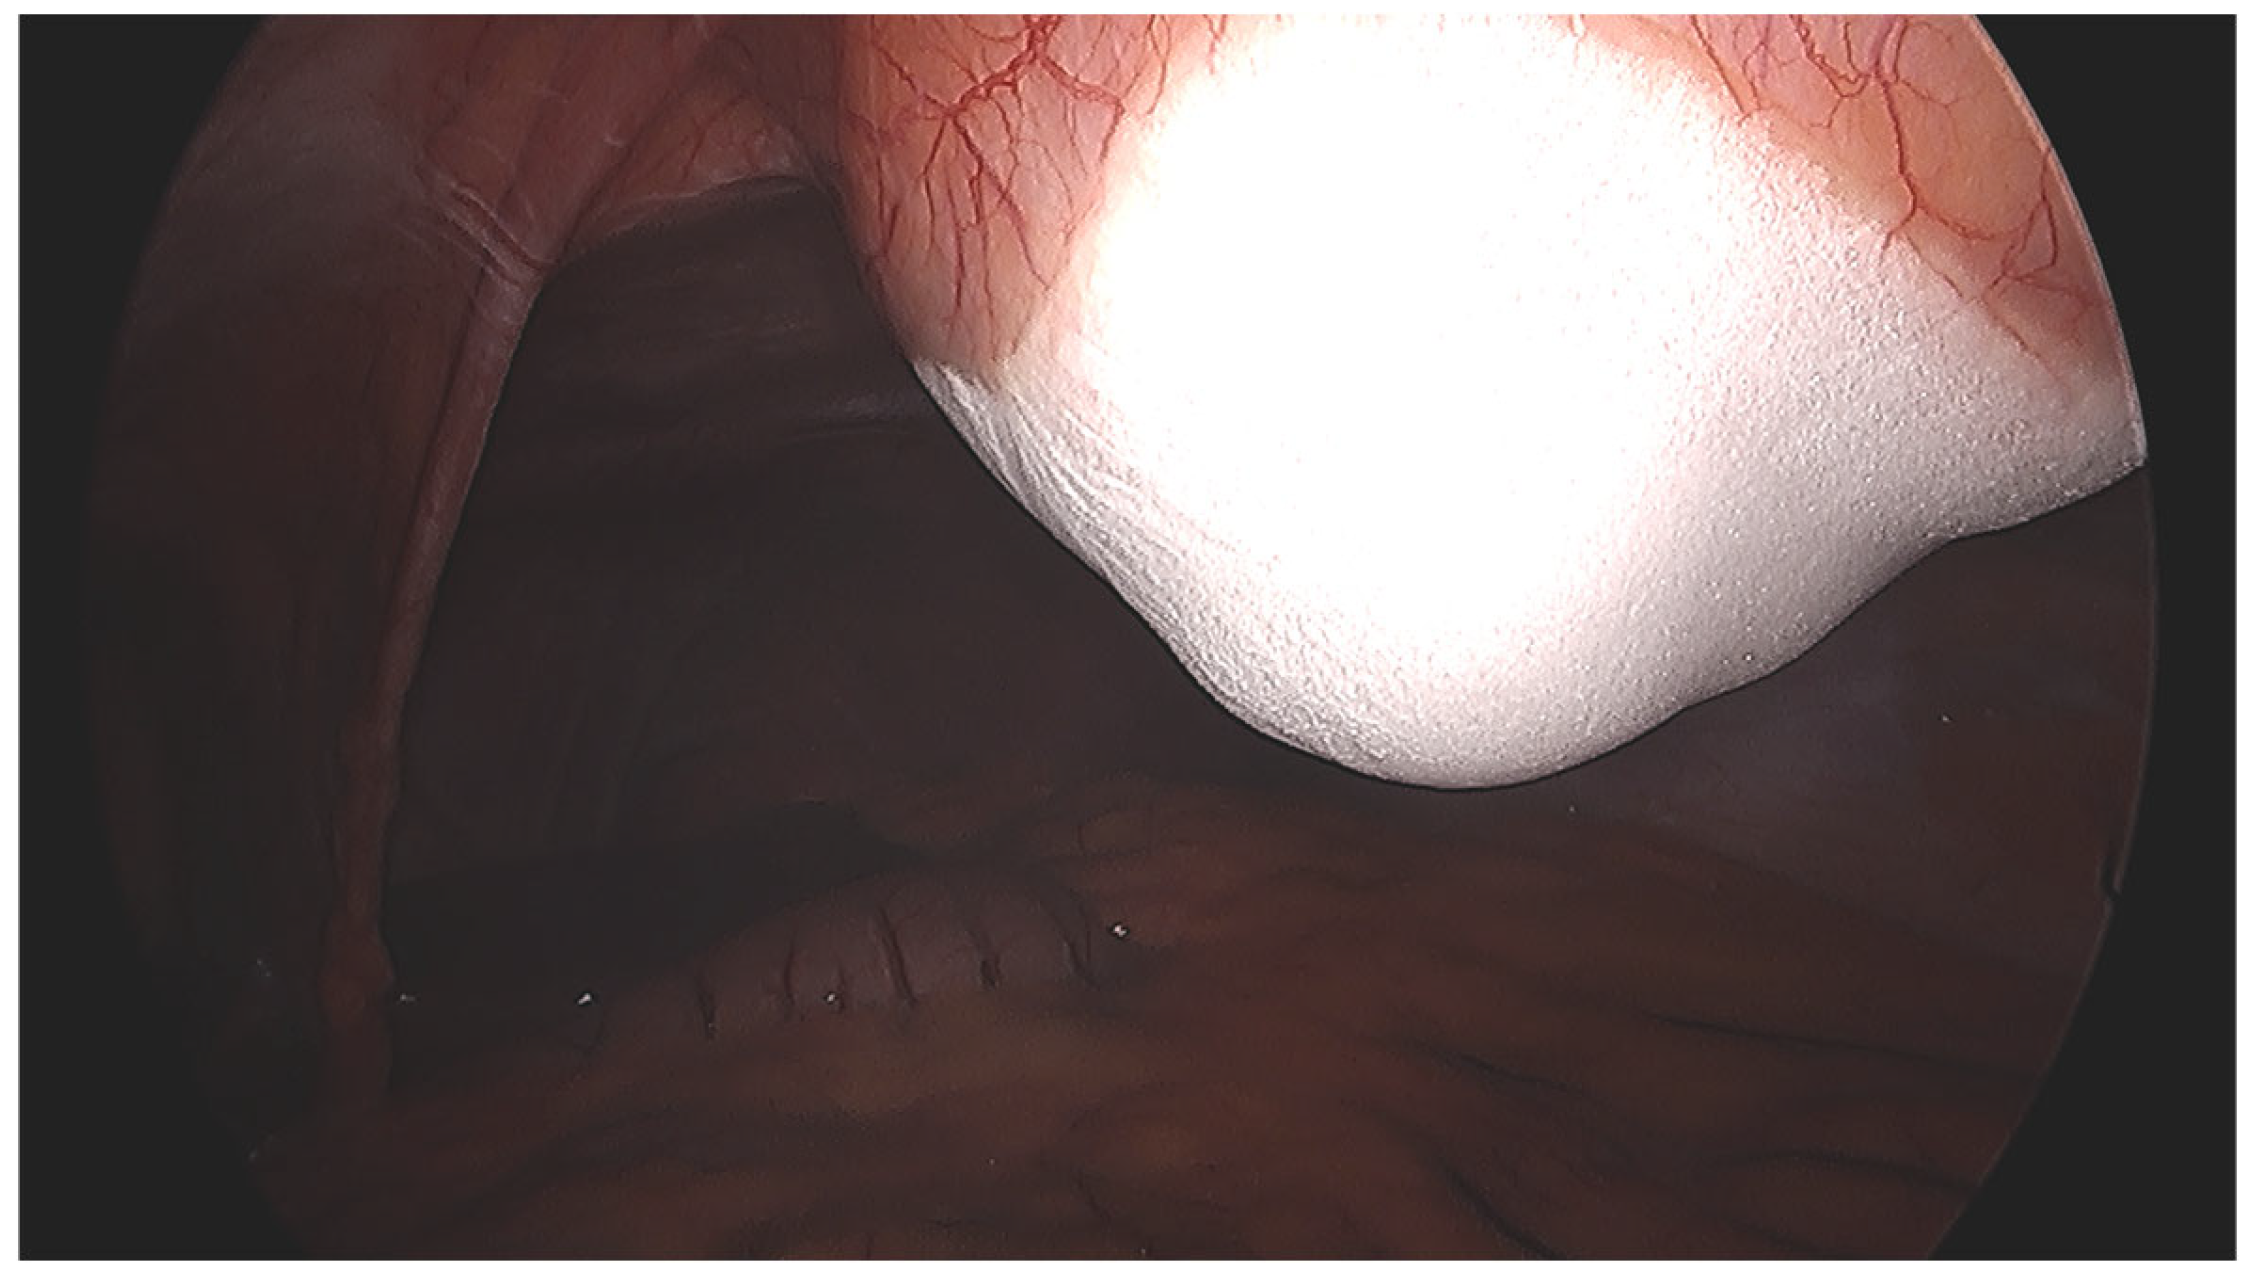

Cryoablation was conducted using a percutaneous, US, and CT-guided approach. Complete ablation was attempted in all cases, ensuring a 5–10 mm safety margin. Tumor puncture and probe advancement were performed under US guidance (Figure 2). Direct tumor puncture was achieved in all cases, and the CO2 did not interfere with US probe placement visualization. The probe placement was confirmed laparoscopically (Figure 3) and using mobile non-contrast CT. A variety of IceSphere and IceForce cryoablation probes (Boston Scientific, MA, USA) were selected based on the tumor size and the manufacturer’s predicted ablation volumes, as assessed by the interventional radiologist, with a spacing of 1–1.5 cm between probes. Hydro-dissection was performed between the tumor and skin to protect the skin, as well as application of sterile heat packs, while CO2 insufflation served as a barrier between the abdominal wall and intraperitoneal organs. Cryoablation was performed using a double-freeze protocol, consisting of two 10 min freezing cycles separated by a 5 min passive thaw. The first freezing cycle was performed using 100% freezing power, while the power in the second freezing cycle was adjusted to protect the skin. Ice ball formation and its extent were monitored laparoscopically (Figure 4), as well as by US and intermittent CT. Active thawing was initiated after the second freezing cycle to ensure resolution of the ice ball before the abdomen was desufflated, and ice spillage into the peritoneal cavity, if present, was suctioned using laparoscopic instruments. At the conclusion of the second freezing cycle, a final non-contrast CT scan was performed to delineate the maximum ablation zone, identify any untreated tumor areas, and confirm the absence of injury to adjacent structures. Following the procedure, the patients were transferred to the post-anesthesia care unit and admitted overnight for pain management and observation.

Figure 4.

The ice ball formation and extent were monitored laparoscopically, maintaining a safety of the intraperitoneal organs.